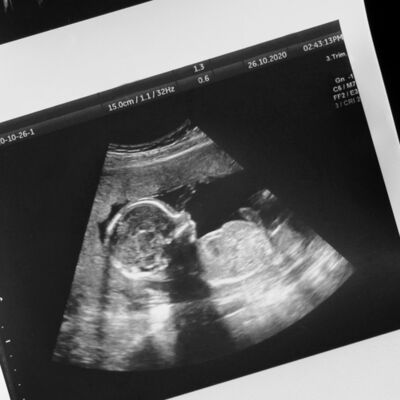

Gebelik haftası 17-18: Mango Zamanı

Gebelik günlüğü: 19. hafta - Hoş Geldin Linea Nigra

Gebelik Günlüğü 21. hafta